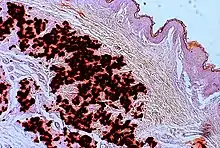

- Diagnostic histopathological changes in lesional skin: Calcified elastic fibers in the mid and lower dermis, confirmed by positive calcium stain

| Pseudoxanthoma elasticum | LM: Mid-dermal calcification and fragmentation of elastic fibers EM: Mineralization in elastic fiber core |